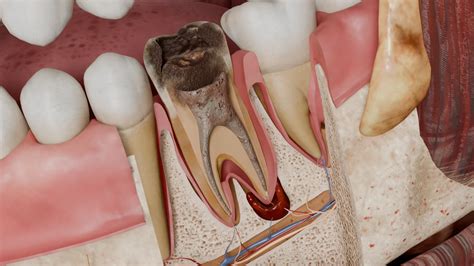

La periodontitis apical es una enfermedad de los tejidos periapicales de etiología bacteriana. Su tratamiento requiere erradicar los microorganismos del conducto radicular y obturarlo para lograr la reparación posterior.

Lesión periapical. Fuente: amorpordientes.com